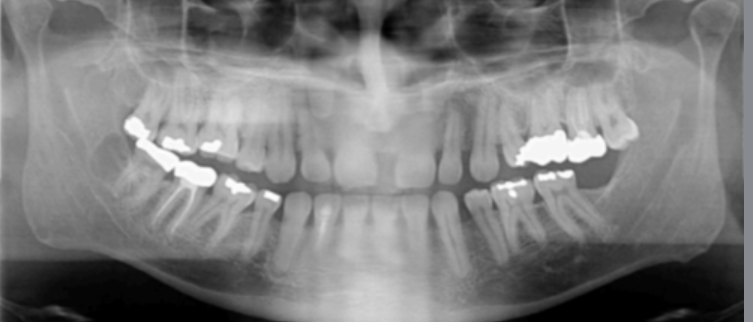

error

chin up